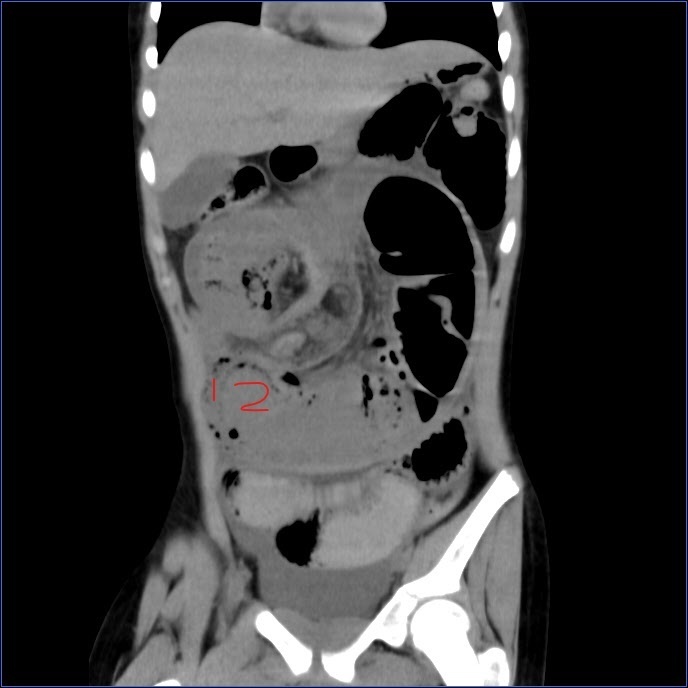

CT检查显示患者肠套叠和多发息肉。(图片由医院提供)

儿科、普外科及手术室紧密配合,迅速完成了术前准备,将患儿送到手术室。由杨俊杰副主任医生带领的手术团队迅速进行剖腹探查,发现患者近1米小肠套叠坏死,黏膜完全脱出,肠内容物均为黑色坏死组织。手术医生迅速减压后离断坏死小肠,并继续探查发现小肠多处息肉及一段套叠梗阻小肠,且经过复位后仍有梗阻,手术团队果断决定切除两段梗阻小肠并进行吻合,同时将触及的小肠息肉切除送检。